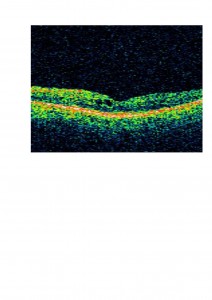

En este paciente decidimos tratar el edema macular cistoide previo a la cirugía de cataratas con acetazolamida oral debido a que muy probablemente iba a empeorar tras la cirugía. En la OCT os mostramos cómo disminuyó el edema:

Volvimos a aumentar la dosis de acetazolamida oral asociada a antinflamatorios no esteroieos tópicos (diclofenaco colirio) y el edema disminuyó:

Después de varios meses, la acetazolamida dejó de hacer efecto y el edema recidivó parcialmente. Suspendimos el tratamiento pero el paciente mantiene, 2 años después, una agudeza visual de 0,5 en ambos ojos y consideramos que la acetazolamida nos ayudó en el control perioperatorio del edema.